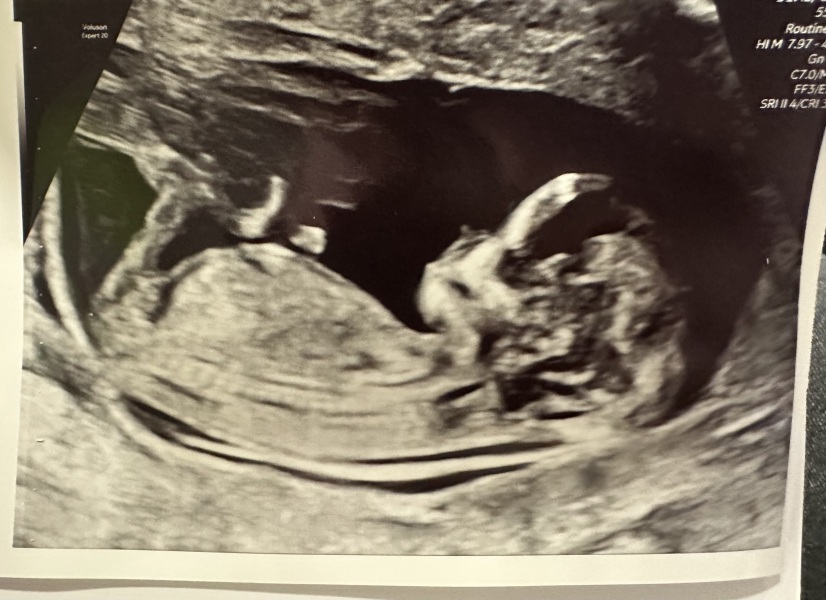

Had my 12 week scan this morning and all good here too. Baby was not cooperating and kept lying with their back to the probe so I was doing a lot of gymnastics on the bed trying to get them to flip over 😂 Scan date matches my lmp date of 12+1 so I'm due 17th June.

Congrats ladies! I was measuring right on time at 12+4 and was very very relieved. We aren’t sure what this one is looking like as skull is saying boy but spine is straight so girl? Maybe someone can do it better than me?

I had my scan today and had to do this too! I had no idea that it was even a thing 😂 Thankfully all seemed well, baby is measuring ahead from the date of my embryo transfer so I'm currently 13 weeks 2 days, with a due date of 10th June. We did the combined screening too, but NT was well within normal range so feeling optimistic for the first time this pregnancy! Hopefully the results won't take too long.